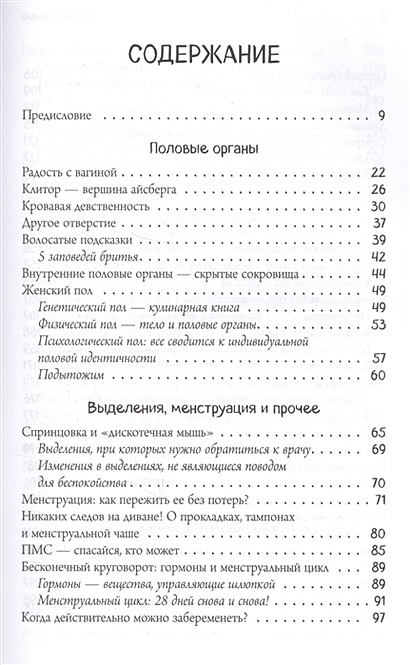

– существует ли пресловутая точка G;

– в каких позах проще всего достичь оргазма и действительно ли вагинальный оргазм лучше клиторального;

– какие контрацептивы считаются самыми надежными;

– всё, что вам нужно знать о заболеваниях половой сферы;

– и, наконец, так ли уж месячные необходимы женскому организму или можно прекрасно обойтись и без них?